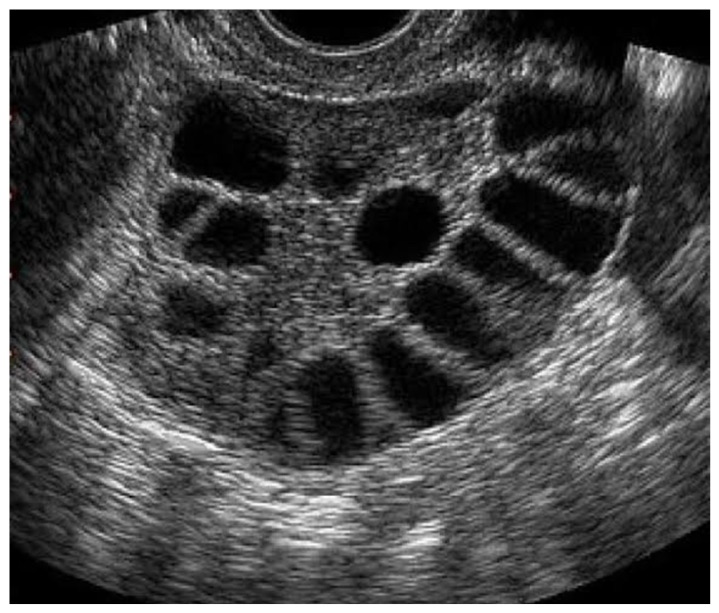

- 초음파 검사 : 질식 초음파를 통해 난소의 상태를 확인하고, 다낭성 난소의 소견을 관찰합니다. 생리 주기가 불규칙한 여성에서 자주 시행됩니다.